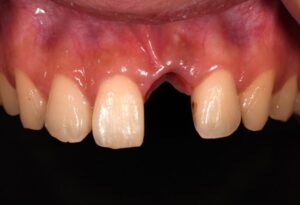

前歯3本欠損症例

前歯3本欠損症例 BEFORE AFTER 46歳女性/上3本欠損/インプラント埋込手術 【治療内容】 前歯3本に根尖病…